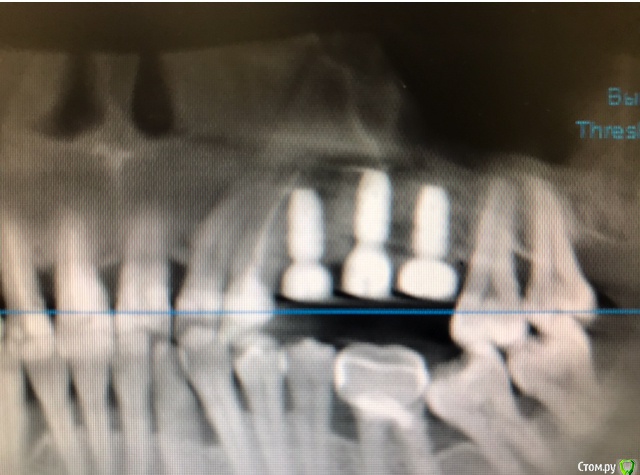

колесников Опубликовано 16 марта, 2019 Автор Поделиться Опубликовано 16 марта, 2019 (изменено) Ну как бы тут все очевидно. Слева стала костью,справа нет. Но должен вам отметить,что даже в случае неудачи (как кажется)потери нет. Задача стояла не увеличить объём для имплантации или укрыть Имплант,а снять напряжение с вершины гребня и дать созреть десне. Имплант в нативной кости,он интегрирован,десна успела созреть за это время,возможно будет не так объёмно как хотелось бы,но у меня в запасе этап раскрытия ,фдм зарос ,есть с чем поработать. Все что не интегрировалось ,лизируется самостоятельно,выскребать ничего не нужно,ещё подождать. Изменено 16 марта, 2019 пользователем колесников Ссылка на комментарий